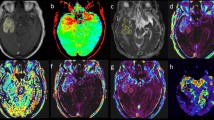

A comparative analysis of APT MRI and SWI in identifying ICH

Figures 1, 2 and 3 showed the imaging manifestations of ICH at hyperacute, acute and subacute stages, respectively. Table 1 quantitatively compared the APT-weighted (APTw), magnetization transfer ratio (MTR)(3.5 ppm) and SWI signal intensities between ICH at hyperacute, acute and subacute stages and the corresponding contralateral normal brain tissue. The APTw signal intensity was significantly higher in the ICH at hyperacute, acute and subacute stages than that in the contralateral normal brain tissue (all p < 0.001). The MTR(3.5 ppm) signal intensity was significantly lower in the ICH at hyperacute, acute and subacute stages than that in the contralateral normal brain tissue (p = 0.03, 0.01 and <0.001, respectively). The SWI signal intensity was significantly lower in the ICH at hyperacute and acute stages than that in the contralateral normal brain tissue (p = 0.03 and 0.02, respectively), but we observed no significant difference between the subacute ICH and the contralateral normal brain tissue (p = 0.11). After Bonferroni corrections for multiple comparisons, the APTw signal intensity was significantly higher in the hyperacute ICH than that in the subacute ICH (p = 0.014).

The hematoma shows mixed-signal on (a) T1w image and (b) T2w image. (c) Susceptibility weighted imaging (SWI) image shows an isointense center with a hypointense periphery. (d) Amide proton transfer (APT) image shows hyperintense signal. (e) MTR(3.5 ppm) image shows hypointense signal. (f) Z spectra map. (g) Z spectra asymmetry curve map.

The hematoma shows isointense signal on (a) T1w image and hyperintense signal on (b) T2w image. (c) SWI image shows a hyperintense center with a hypointense periphery. (d) APT image shows hyperintense signal. (e) MTR(3.5 ppm) image shows hypointense signal. (f) Z spectra map. (g) Z spectra asymmetry curve map.